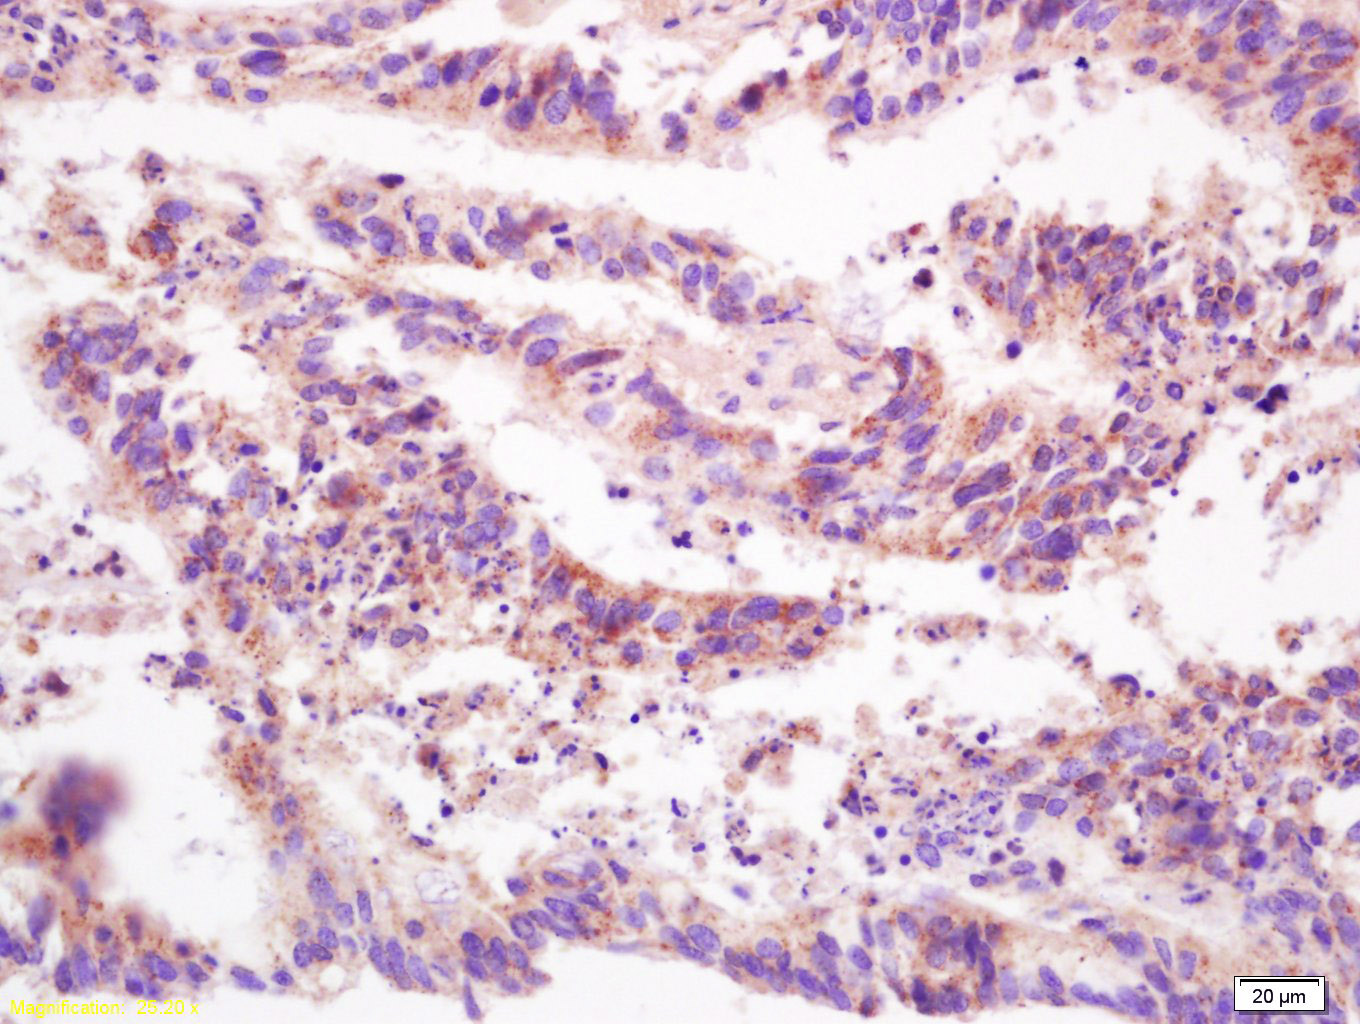

Tissue/cell: human lung carcinoma; 4% Paraformaldehyde-fixed and paraffin-embedded; Antigen retrieval: citrate buffer ( 0.01M, pH 6.0 ), Boiling bathing for 15min; Block endogenous peroxidase by 3% Hydrogen peroxide for 30min; Blocking buffer (normal goat serum,C-0005) at 37℃ for 20 min; Incubation: Anti-PTP/PTPase/CD148 Polyclonal Antibody, Unconjugated(bs-2567R) 1:200, overnight at 4°C, followed by conjugation to the secondary antibody(SP-0023) and DAB(C-0010) staining

Tissue/cell: human colon carcinoma; 4% Paraformaldehyde-fixed and paraffin-embedded; Antigen retrieval: citrate buffer ( 0.01M, pH 6.0 ), Boiling bathing for 15min; Block endogenous peroxidase by 3% Hydrogen peroxide for 30min; Blocking buffer (normal goat serum,C-0005) at 37℃ for 20 min; Incubation: Anti-PTP/PTPase/CD148 Polyclonal Antibody, Unconjugated(bs-2567R) 1:200, overnight at 4°C, followed by conjugation to the secondary antibody(SP-0023) and DAB(C-0010) staining